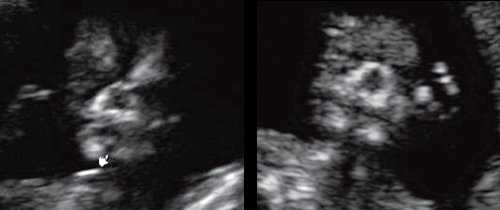

Гипоплазия нижней челюсти при различных нехромосомных синдромах обычно встречается в сочетании со скелетными дисплазиями и мышечно-скелетными аномалиями: синдром Пьера Робена (рис. 3), Тичера - Коллинза (Франческетти), акрофасциальный дизостоз, цереброкостомандибулярный синдром, ахондрогенез (рис. 4), ателостеогенез, кампомелическая дисплазия, диастрофическая дисплазия (рис. 5), синдром множественных птеригиумов, синдром Пены - Шокейра и др. Наличие микрогнатии характерно для синдрома Карпентера, синдрома Фринса, синдрома Меккеля - Грубера, гидролетального синдрома, синдрома Миллера - Дикера, синдрома Нунан, синдрома Секкеля, Рубинштейна - Тейби и др. Большинство из описанных синдромов имеют аутосомно-рецессивный либо аутосомно-доминантный тип наследования [10, 11].

Рис. 3. Микрогнатия у плода при синдроме Пьера Робена в 13 нед беременности.

Рис. 4. Микрогнатия у плода с ахондрогенезом в 13 нед беременности.

Рис. 5. Микрогнатия у плода с синромом диастрофической дисплазии в 12 нед беременности.